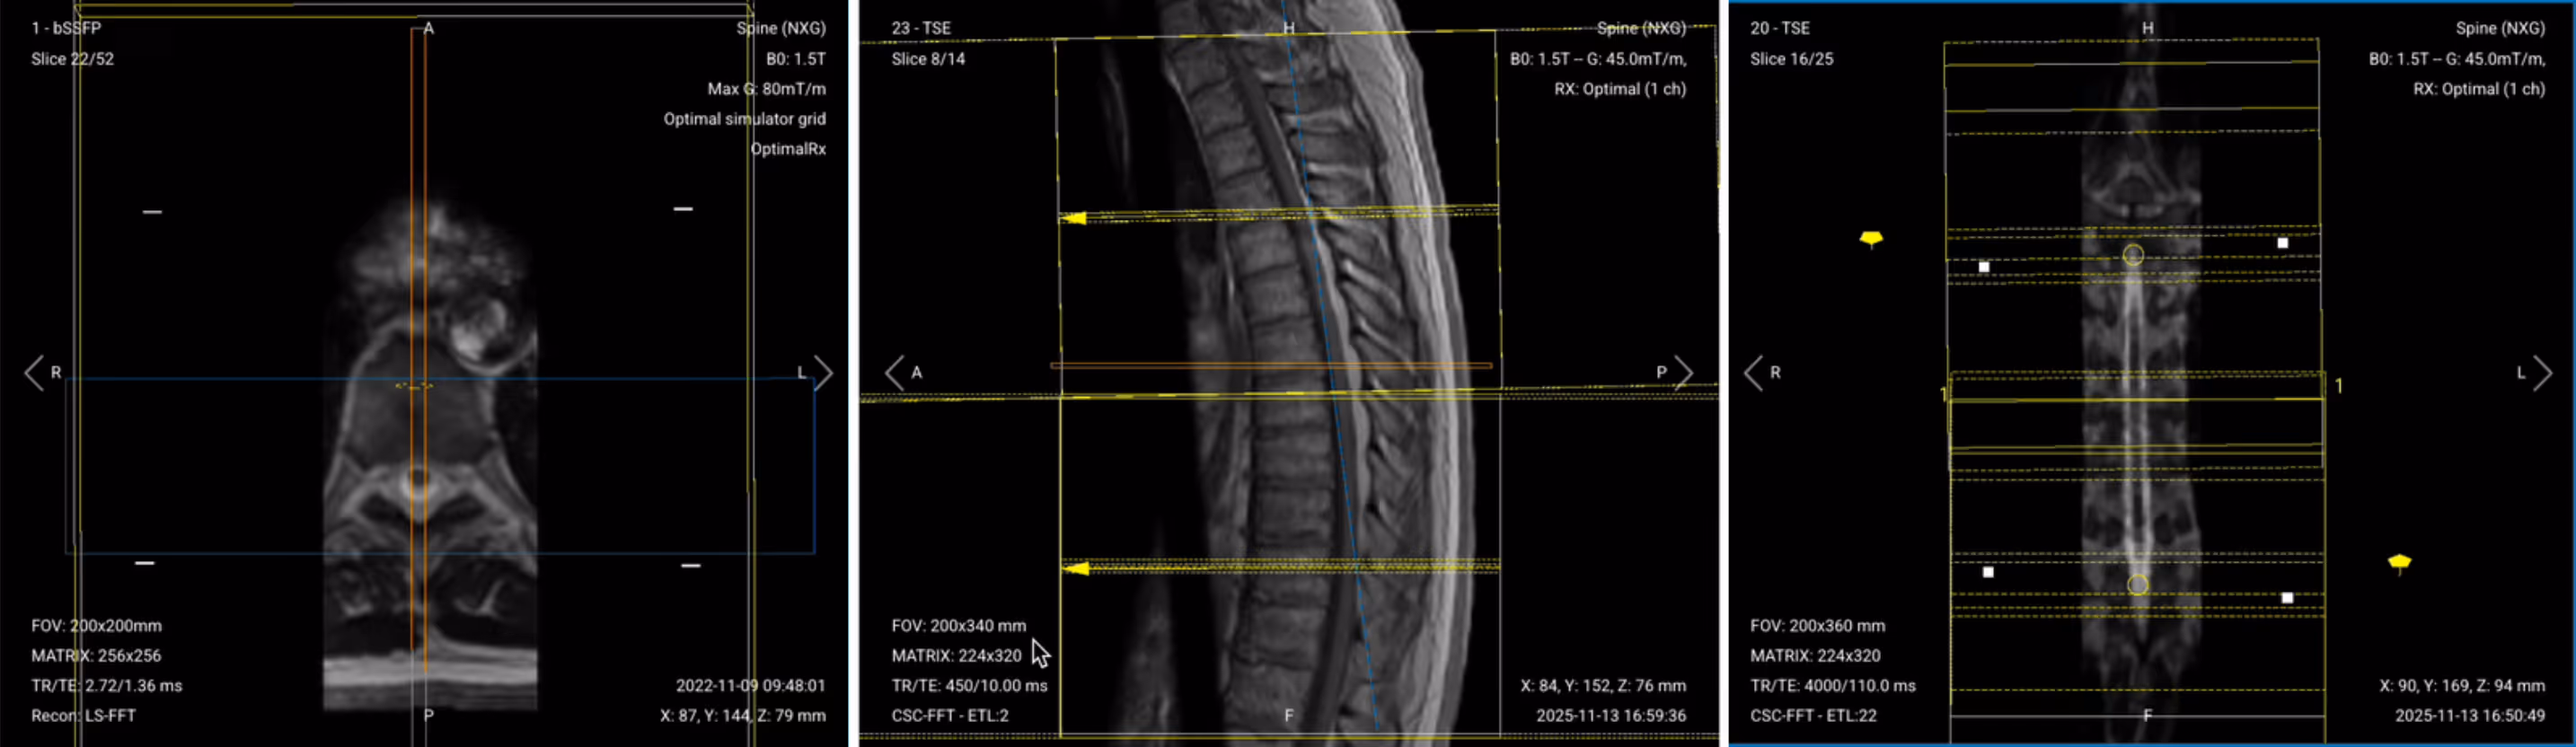

✅ Correct Planning:

Planning Instructions:

Parameters for Sagittal T2 TSE:

| Parameter | Recommended Values | Why These Values |

|---|---|---|

| Echo Time (TE) | 100–120 ms | Longer TE is required for T2 contrast. |

| Repetition Time (TR) | 4,000–6,000 ms | Longer TR is required for T2 contrast. |

| Field-of-View (FOV) | 200 × 340 mm | Rectangular FOV optimized for the thoracic spine's vertical extent, covering superior-to-inferior while minimizing anterior-posterior to reduce scan time. |

| Matrix | 224 × 320 | Medium matrix size provides sufficient resolution while maintaining short scan time and high SNR. |

| Foldover Direction (Phase) | Foot-to-Head (FH) / Superior-to-Inferior | Aligns with cerebrospinal fluid flow to reduce flow artifacts. |

| Number of Slices | 14–18 | Enough slices to cover the thoracic spine from right to left. |

| Slice Thickness | 4 mm | Medium thickness provides good resolution without sacrificing scan time or SNR. |

| Slice Gap | 0.4 mm | 10% of slice thickness prevents crosstalk while ensuring continuity. |

| NEX / Averages | 1–2 | Provides enough SNR while keeping scan time short. |

| Turbo Factor / ETL | 16–24 | Higher turbo factor enhances T2 contrast and reduces scan time. |

| Bandwidth | 50,000 Hz | Medium bandwidth balances SNR with chemical shift artifact reduction. Lower than typical values to improve SNR in the challenging thoracic region. |

| Fold-over Suppression | Yes | Prevents aliasing or wrap-around artifacts. |

✅ Sagittal T2 TSE of Thoracic Spine – Correct Image Example:

Things to Look for in Sagittal T2: